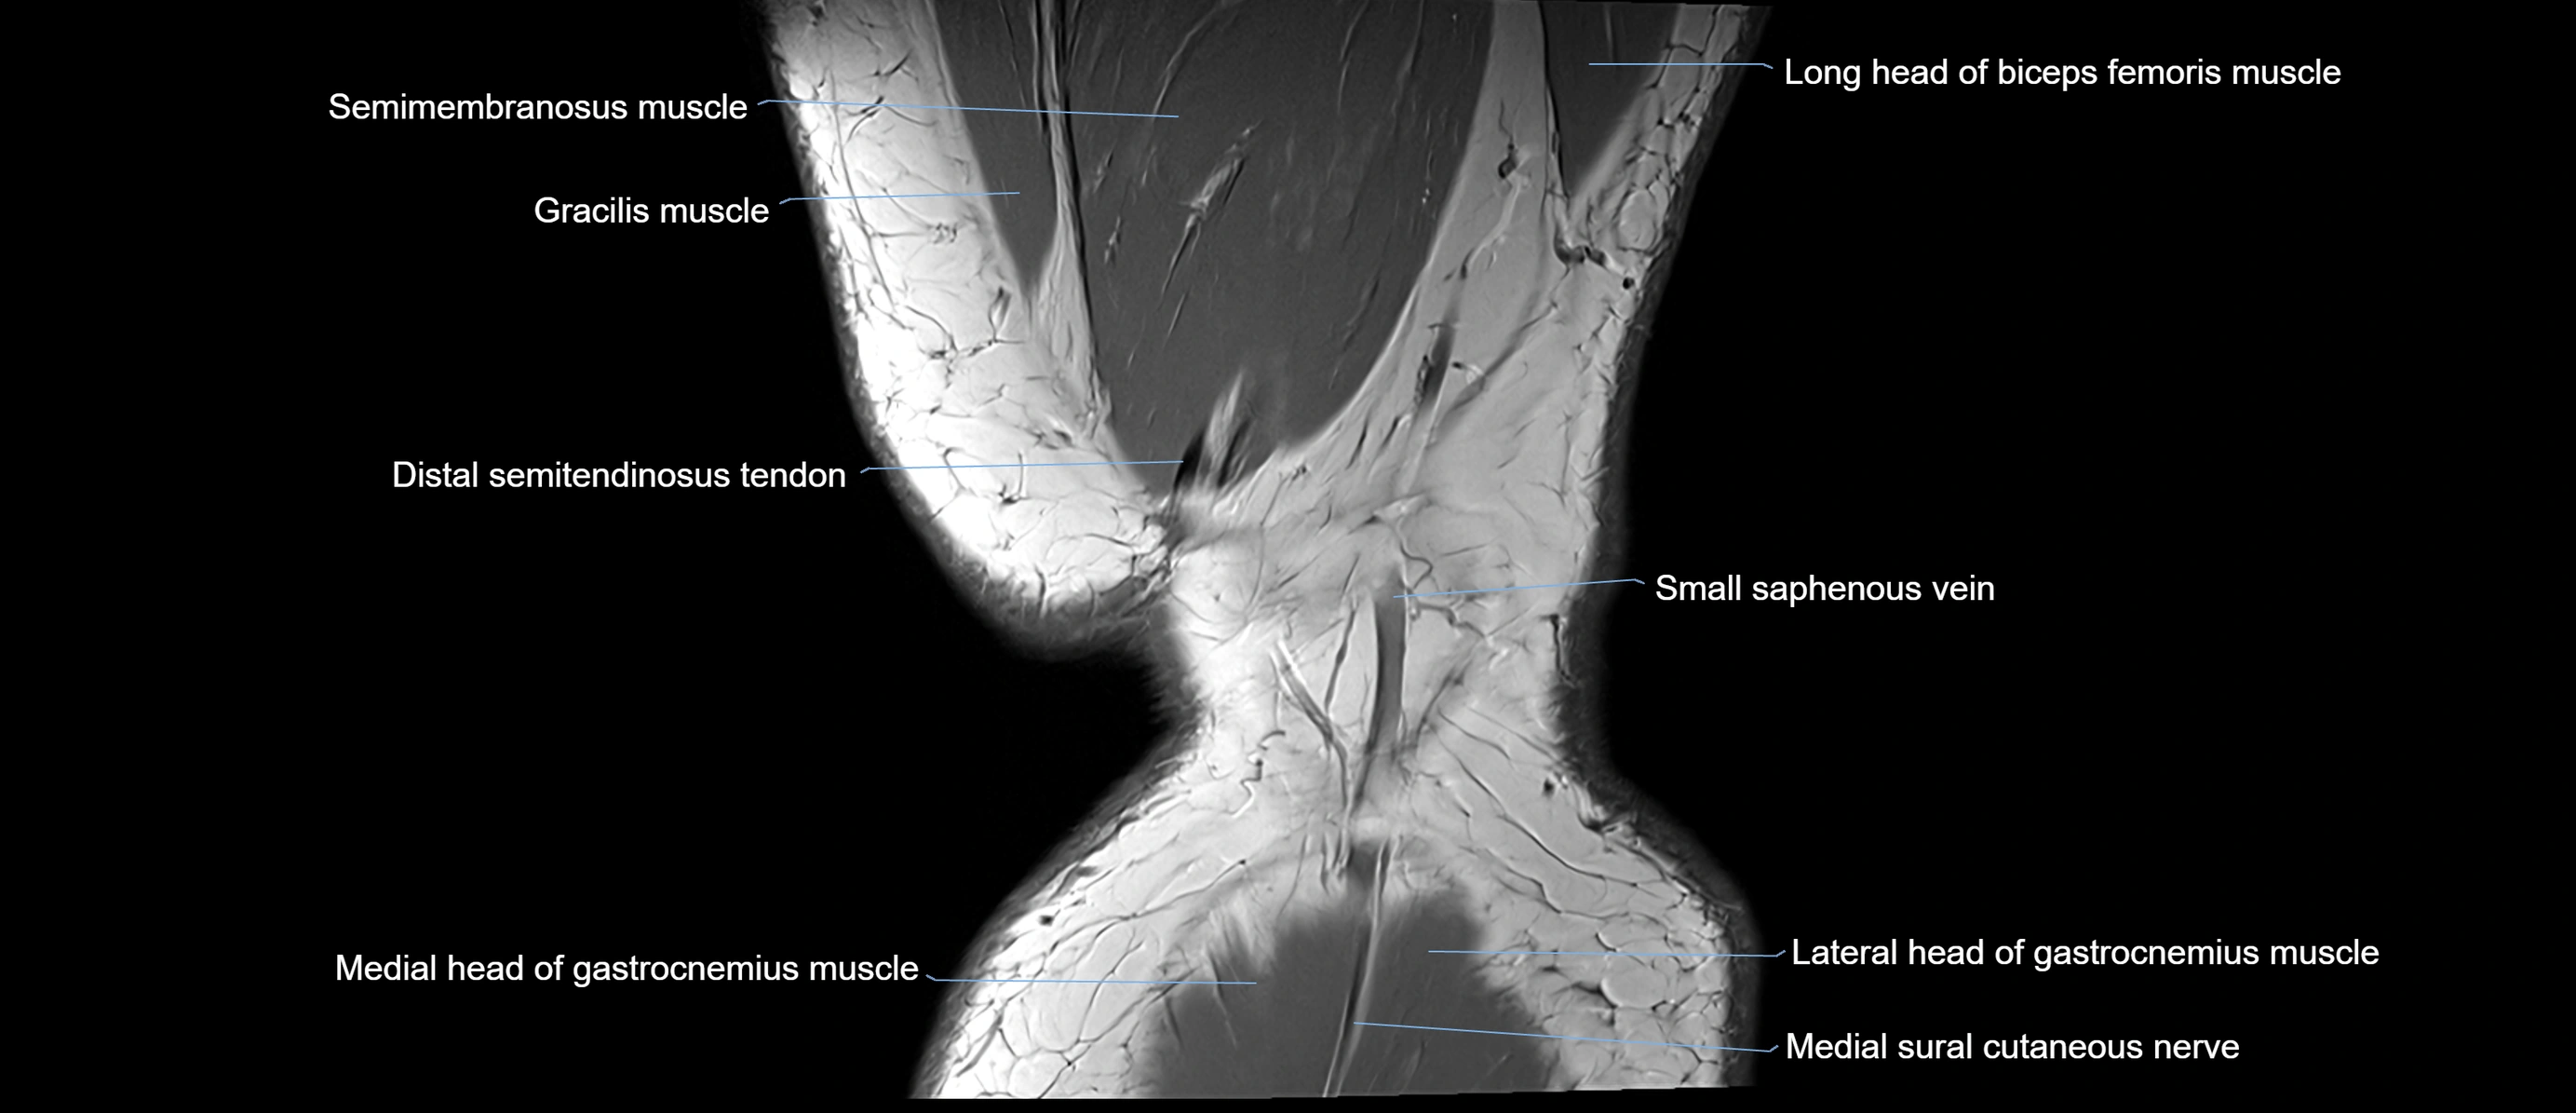

- Distal semitendinosus tendon

- Medial head of gastrocnemius muscle

- Medial sural cutaneous nerve

- Small saphenous vein